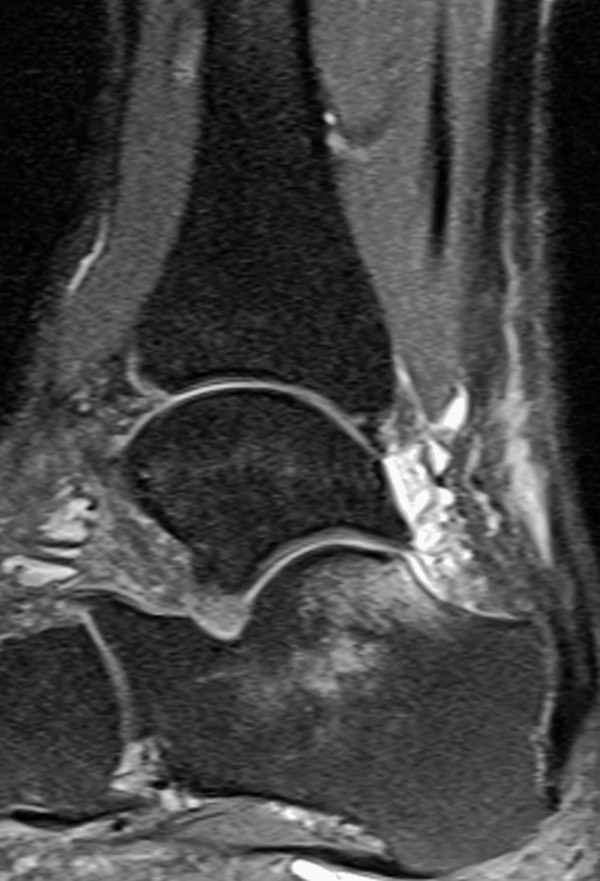

• MRT zur Beurteilung der Achillessehnendegeneration und zur Bestimmung der Defektstrecke (Abbildung 1).